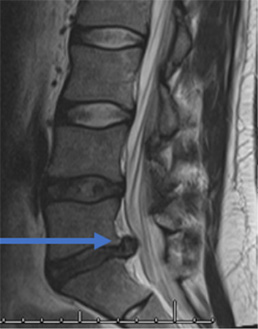

31 year old man presents with excruciating right leg pain. MRI shows a right L5-S1 disc herniation on the right (see arrow). The left image is a sagittal view where you are seeing the spine from the side. The right image is looking at a cross section of your spine. On this view the right side is the left of the image and vice versa.

After minimally invasive surgery, the disc herniation is removed. The remaining “normal” disc is left alone.